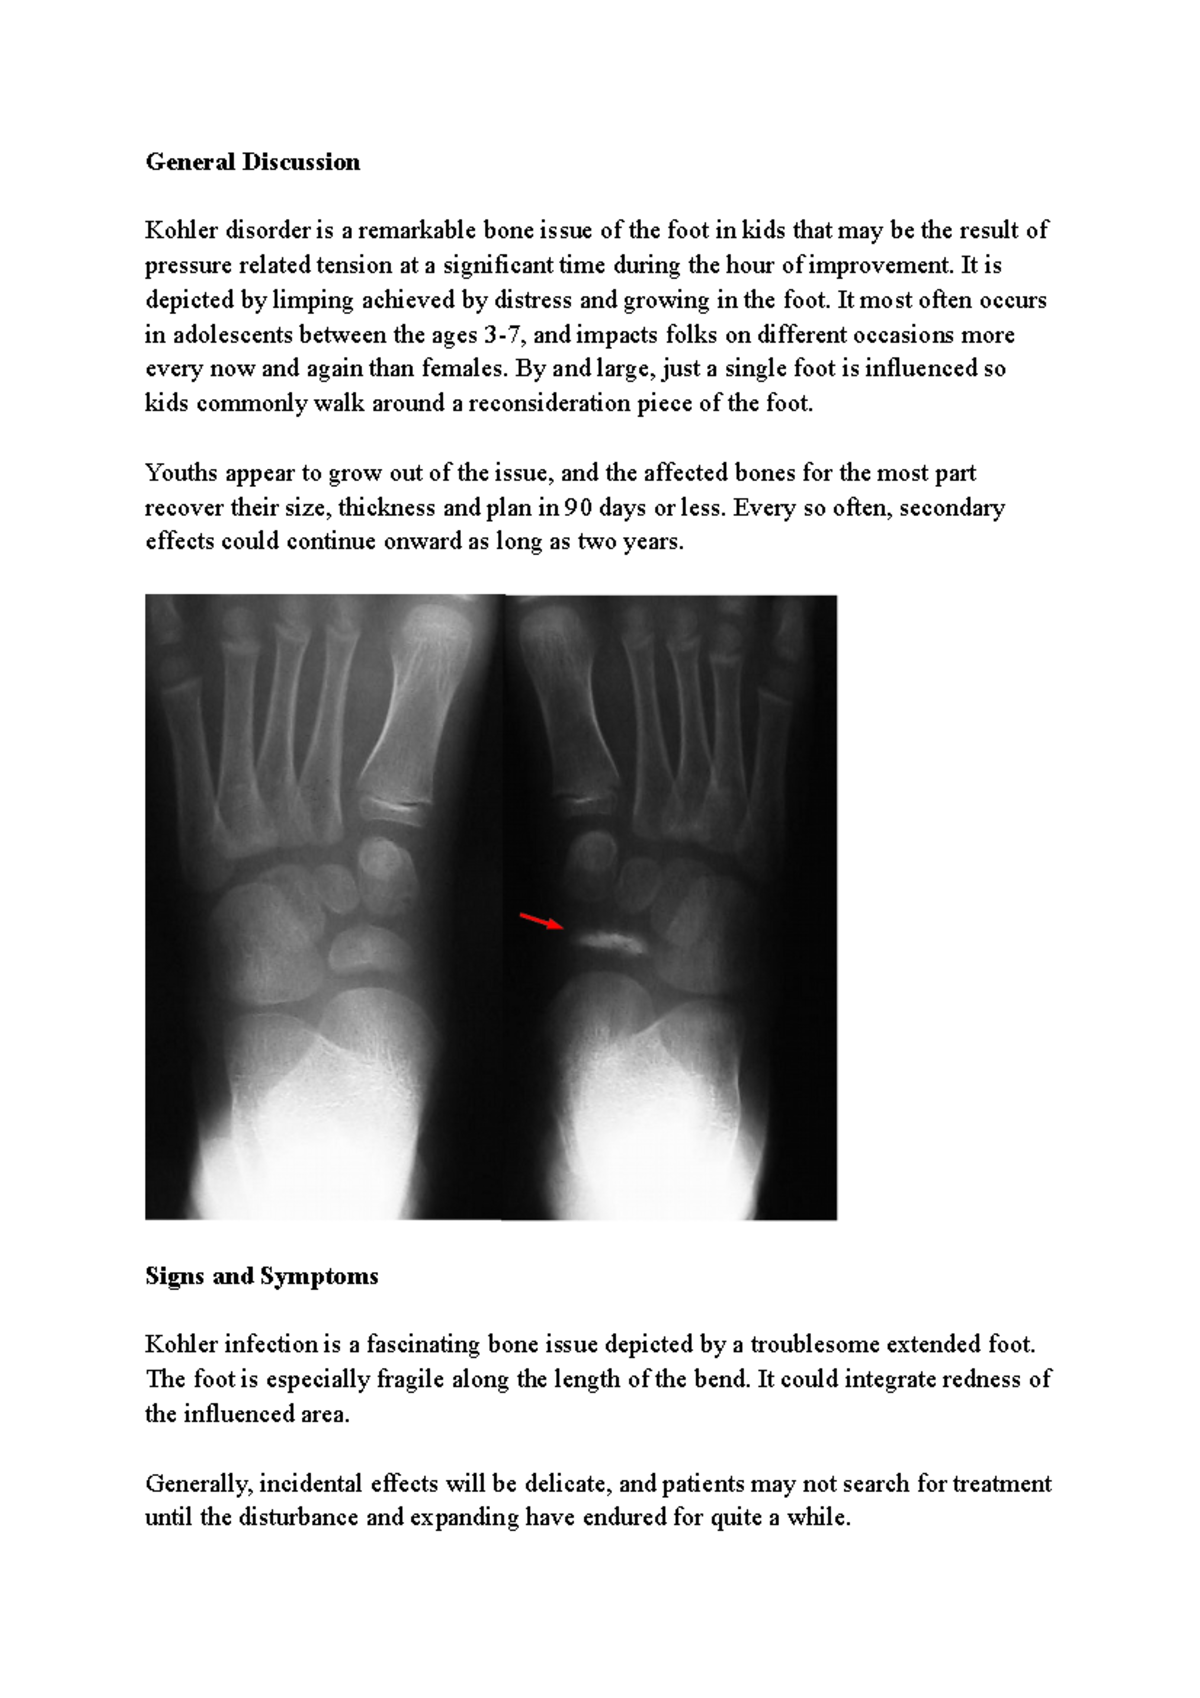

Kohler Disorder General Discussion Kohler disorder is a remarkable Kohler's Disease Child It causes inflammation of an outgrowth to the tarsal. Kohler's disease is a rare idiopathic condition caused by avascular necrosis of the navicular bone that occurs in young children. The foot becomes swollen and painful, and the arch of the foot. Köhler bone disease usually affects children aged 3 to 5 years (more commonly boys) and typically affects only one. Kohler's Disease Child.